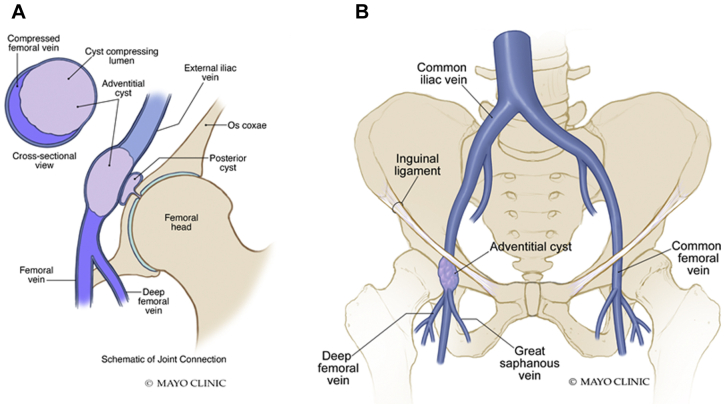

On examination, the patient had palpable pedal pulses and right lower extremity edema from the ankle to the thigh, without varicosities or skin changes. No palpable lymphadenopathy or masses were present in the groin. Anticoagulation was initiated, and thigh-high graduated compression stockings rated at 30 to 40 mm Hg were placed. A repeat ultrasound scan at 6 months demonstrated recanalization of the common femoral and saphenous veins with chronic post-thrombotic changes. Magnetic resonance venography demonstrated a 3-cm cyst anteromedial to the right common femoral vein that was compressing the lumen and another 1.2-cm cyst posterior to the vein and communicating to the hip joint (Figs 1 and 2). A labral tear was identified on the magnetic resonance venogram (Fig 1, C), which possibly contributed to formation of the adventitial cyst.

Fig 2.

A, Illustration demonstrating compression of the vein lumen by the cyst with a connection to the hip joint capsule. B, Schematic diagram demonstrating the location of the adventitial cyst caudal to the inguinal ligament but cephalad to the saphenofemoral junction.